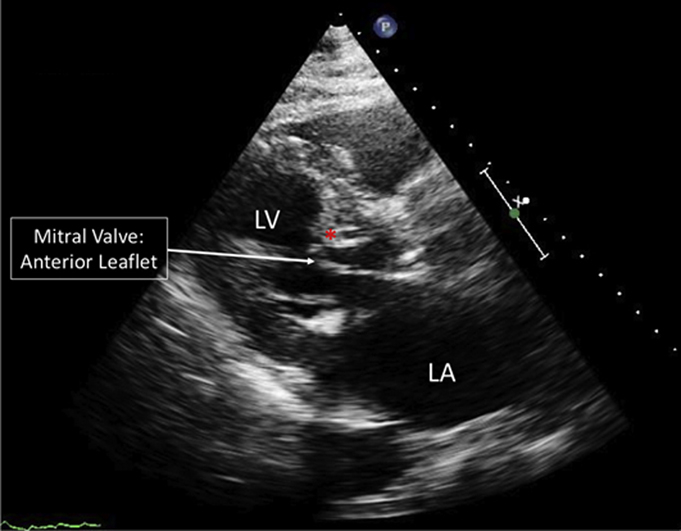

Figure 1.

Pre-Operative Transthoracic Echocardiogram

Parasternal long-axis view of a pre-operative transthoracic echocardiogram demonstrating severe basal septal hypertrophy and systolic anterior motion of the mitral valve. ∗Hypertrophied basal septum. LA = left atrium; LV = left ventricle.

Transthoracic echocardiography (TTE) revealed an ejection fraction of 66%, with LVOT gradients by spectral Doppler of 52 mm Hg at rest and 144 mm Hg with Valsalva. Moderate systolic anterior motion (SAM) of the anterior mitral valve leaflet was observed (Figure 1, Video 1). A transesophageal echocardiogram also demonstrated severe basal septal hypertrophy with SAM of the anterior mitral leaflet, and mild mitral regurgitation caused by HCM (Video 2). Despite cardioversion to normal sinus rhythm and up-titration of medications, the patient continued to have significant dyspnea, suggesting his symptoms were attributable to LVOT obstruction. Because he was deemed a poor surgical candidate due to multiple medical comorbidities, he was referred for alcohol septal ablation (ASA).